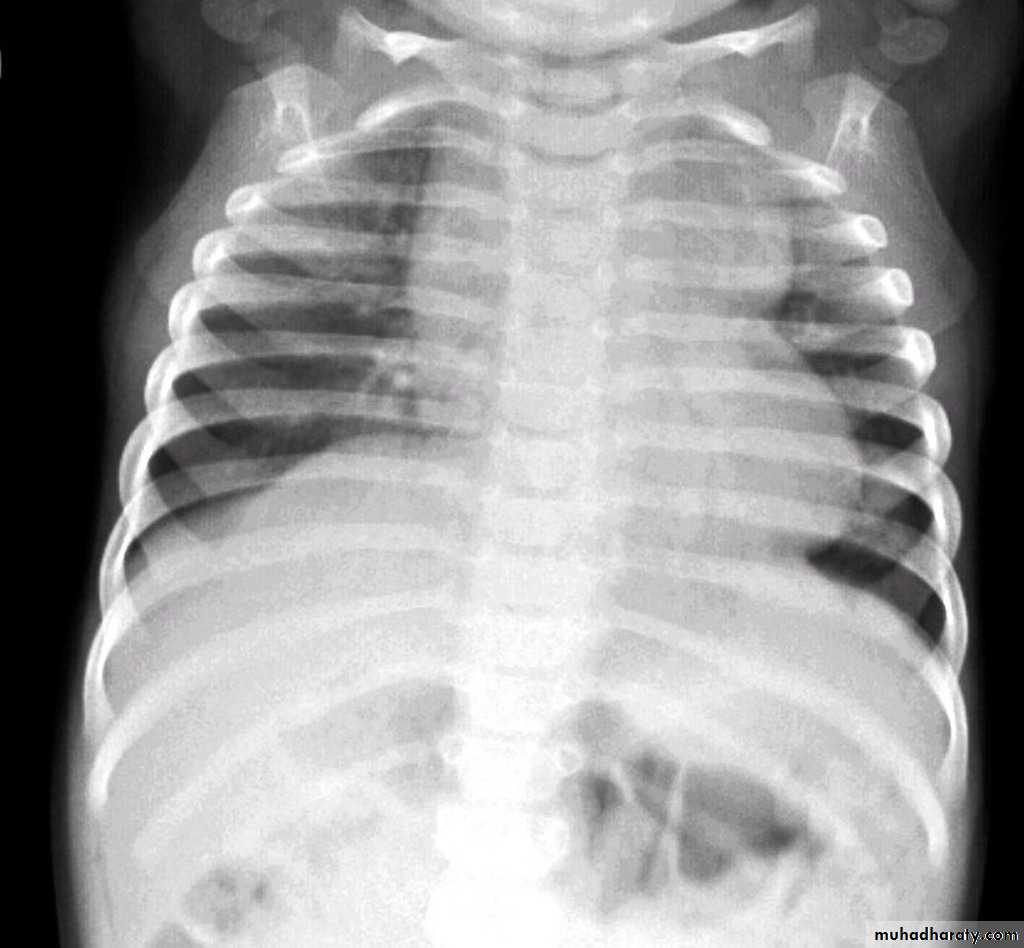

"boot shaped" heart ( TOF )

TOF